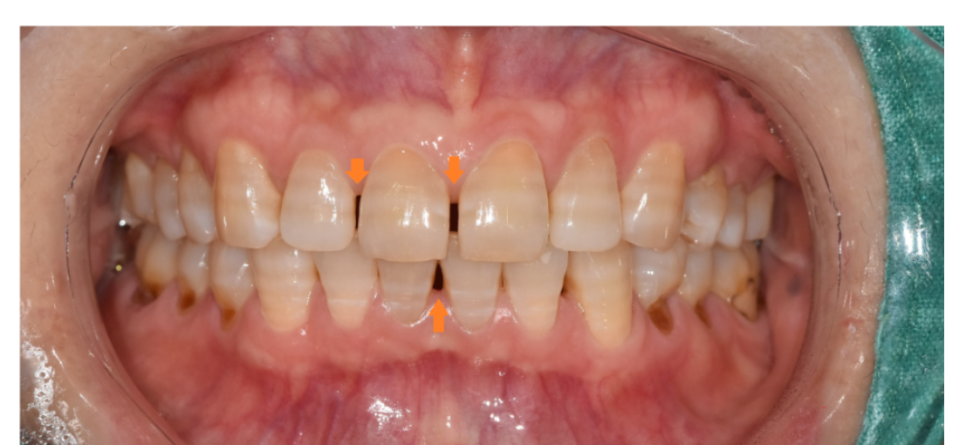

240220 벌어진 치아

✔ 앞니만 살짝 틀어졌거나 벌어졌어요

✔ 웃을 때 보이는 치열이 불만이에요

거울을 보며 살짝 벌어진 틈새

틀어진 치아 한개로 매일 신경쓰고 계신가요?